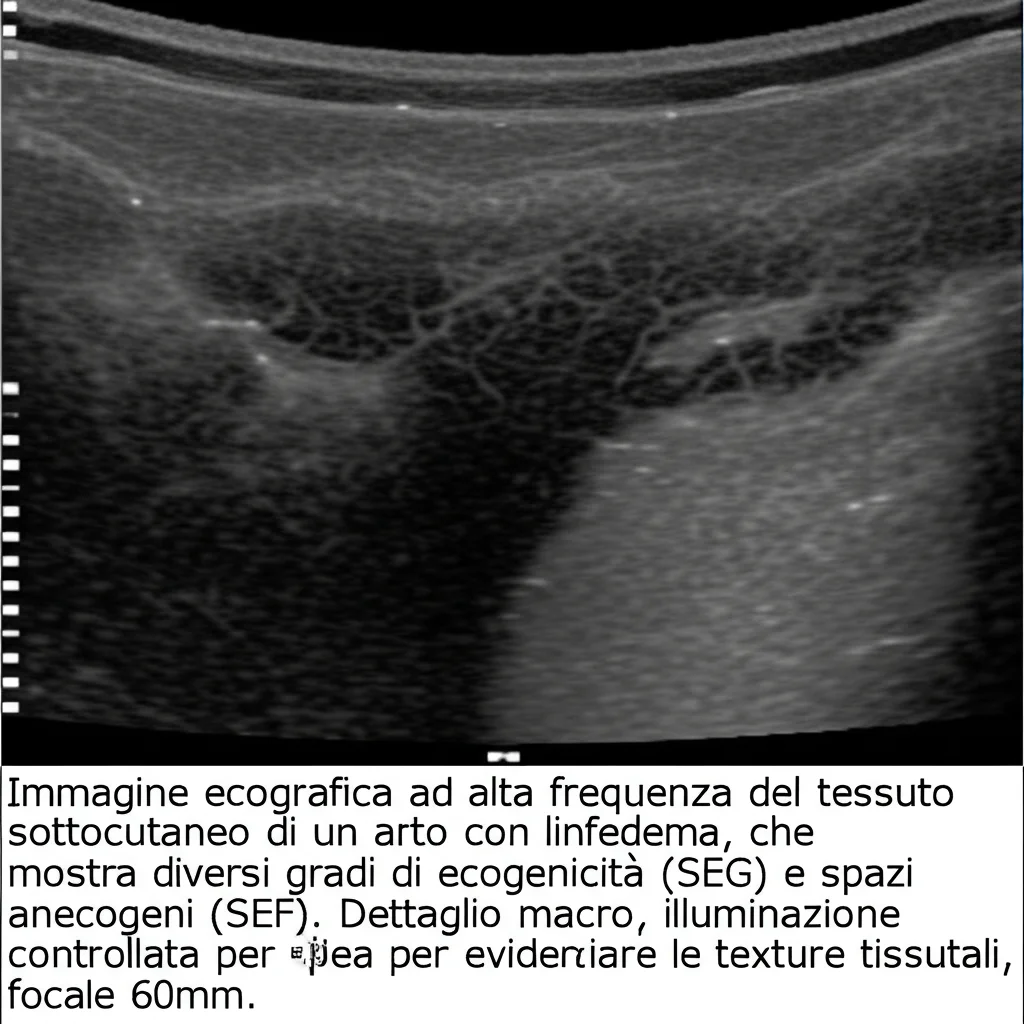

Come facciamo a vedere questi cambiamenti senza dover fare biopsie invasive di continuo? Qui entra in gioco l’ecografia del tessuto sottocutaneo. Non parlo di quelle super sofisticate ad altissima frequenza, che sono fantastiche per vedere i piccoli vasi linfatici ma non sempre disponibili. Parlo della buona vecchia ecografia ad alta frequenza (6-18 MHz), quella che si trova in molti ospedali e cliniche.

Questa ecografia “convenzionale” magari non vede i singoli vasellini linfatici in dettaglio, ma penetra più a fondo nel tessuto sottocutaneo e ci permette di valutare due parametri chiave:

- SEG (Subcutaneous Echogenicity – Ecogenicità Sottocutanea): In pratica, misura quanto il tessuto “riflette” gli ultrasuoni. Si pensa che un SEG più alto indichi una maggiore densità cellulare e più collagene, cioè fibrosi. Viene graduata da 0 (normale) a 2 (molto ecogeno).

- SEF (Subcutaneous Echo-Free Space – Spazio Anecono Sottocutaneo): Questo parametro indica la presenza di “spazi vuoti” agli ultrasuoni, che di solito corrispondono ad accumuli di liquido. Anche questo va da 0 (assente) a 2 (spazi verticali evidenti).